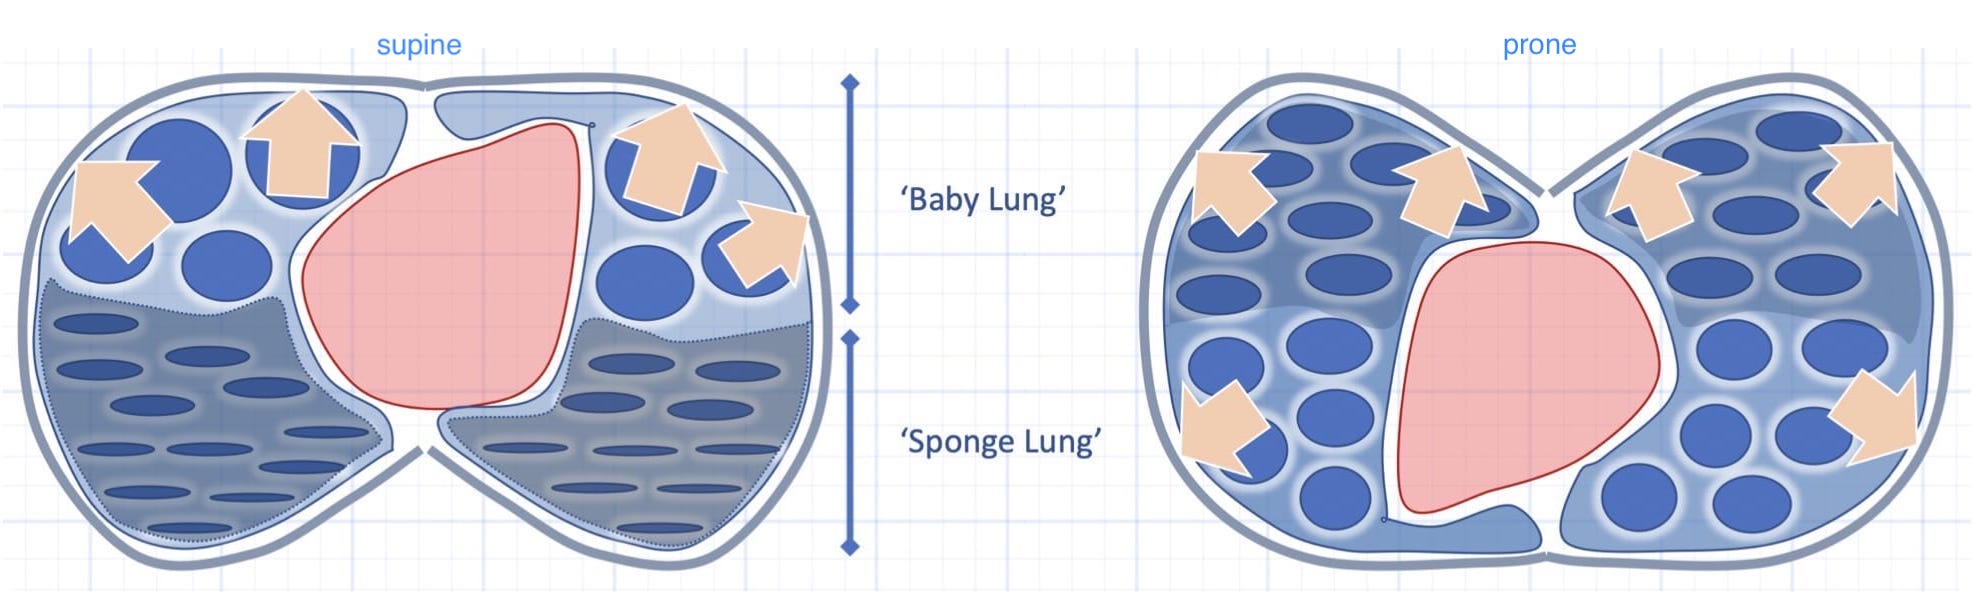

The concepts of (dorsal) “sponge” and (ventral) “baby” lungs are evocative. The size of the ventral aerated lung in ARDS (with the patient supine) suggests a “baby” lung— as conceptualized by Gattinoni et. al.

This lovely explanatory graphic (Figure 7; page 255) is from the free book An Approach to Mechanical Heart-Lung Interaction by Jon-Emile S. Kenny available here.

There is relatively more lung volume in the dorsal lungs.